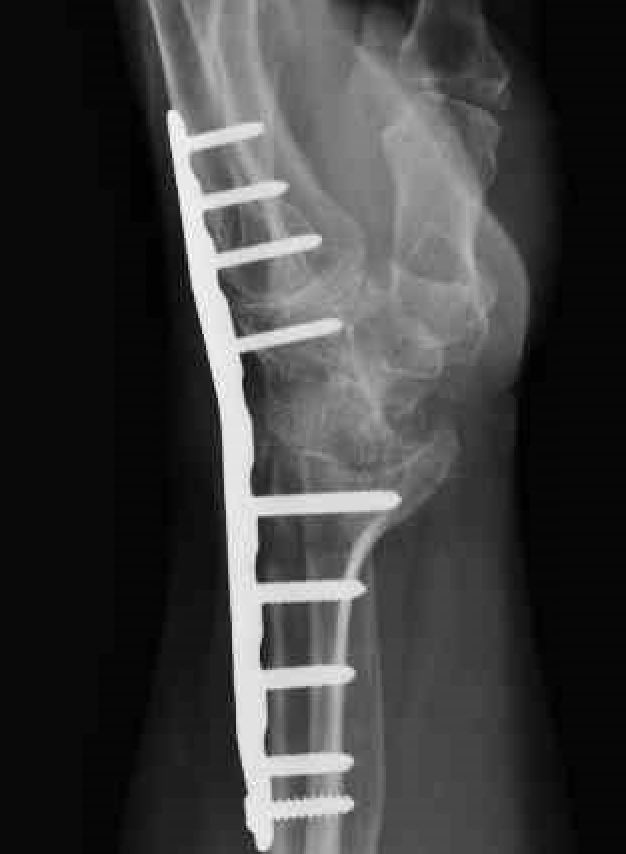

Spanning dorsal plate

Concept

Distal radius to third metacarpal

- fusion radiocarpal & midcarpal +/- fusion of 3rd carpometacarpal joint

- low profile and precontoured plate

- 15 degree dorsal angulation and slight ulna deviation to maximize grip strength

Dorsal plate